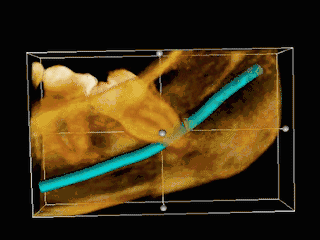

|

TAC 3D de una muela del juicio impactada adyacente al nervio alveolar inferior antes de la extracción de la muela del juicio. | ||

Si el diente no se puede evaluar únicamente con el examen clínico, el diagnóstico se realiza mediante una radiografía panorámica o una tomografía computarizada de haz cónico. Cuando las muelas del juicio no erupcionadas todavía tienen potencial de erupción, se utilizan varios factores predictivos para determinar la probabilidad de que los dientes se impacten. La relación de espacio entre la longitud de la corona del diente y la cantidad de espacio disponible, el ángulo de los dientes en comparación con los otros dientes son los dos predictores más utilizados, siendo la relación de espacio la más precisa. A pesar de la capacidad de movimiento en la edad adulta temprana, la probabilidad de que el diente se impacte puede predecirse cuando la relación entre el espacio disponible y la longitud de la corona del diente es inferior a 1.:[5] 141

La coronectomía es un procedimiento en el que se extrae la corona de la muela del juicio impactada, pero las raíces se dejan intencionadamente en su sitio. Está indicada cuando no hay enfermedad de la pulpa dental ni infección alrededor de la corona del diente, y existe un alto riesgo de lesión del nervio alveolar inferior.[32]